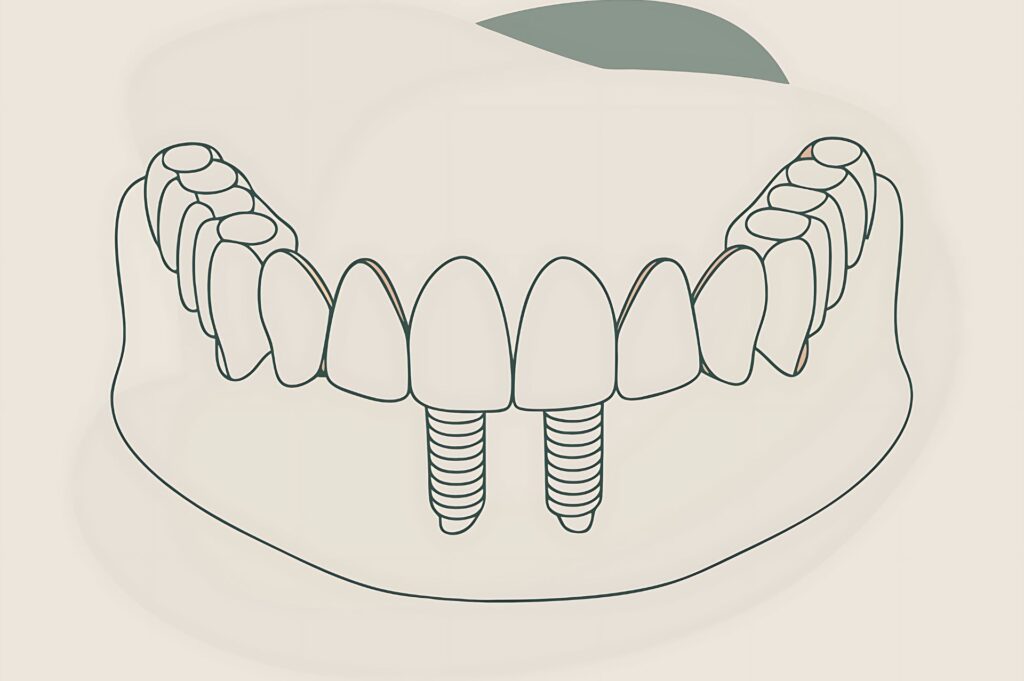

Η διαδικασία τοποθέτησης οδοντικών εμφυτευμάτων στο Oralis Dental Center Θεσσαλονίκη είναι απολύτως ασφαλής και πραγματοποιείται με τις πιο σύγχρονες, ελάχιστα επεμβατικές τεχνικές.

Η διαδικασία τοποθέτησης οδοντικών εμφυτευμάτων ολοκληρώνεται σε σύντομο χρονικό διάστημα και προσφέρει οριστική, λειτουργική και αισθητική αποκατάσταση του στόματος, χαρίζοντας ξανά φυσικό χαμόγελο και αυτοπεποίθηση στον ασθενή.

Κάθε στάδιο στην διαδικασία τοποθέτησης οδοντικών εμφυτευμάτων, από τη διάγνωση και τον σχεδιασμό έως την τοποθέτηση και αποκατάσταση, πραγματοποιείται με απόλυτη ακρίβεια και σύγχρονο τεχνολογικό εξοπλισμό, προσφέροντας ένα μόνιμο, υγιές και φυσικό αποτέλεσμα.

Πρόκειται για το στάδιο κατά το οποίο πραγματοποιείται η τοποθέτηση των οδοντικών εμφυτευμάτων στο στόμα του ασθενούς. Σε ορισμένες περιπτώσεις, ο Γναθοχειρουργός μπορεί να προχωρήσει και σε προσωρινή προσθετική αποκατάσταση, ώστε να διατηρηθεί η αισθητική του χαμόγελου μέχρι την ολοκλήρωση της θεραπείας.

Για τη μέγιστη ασφάλεια και ακρίβεια, χρησιμοποιείται Ειδικός Χειρουργικός Οδηγός, ο οποίος καθοδηγεί τη διαδικασία με απόλυτη προβλεψιμότητα. Η διάρκεια τοποθέτησης είναι σχετικά σύντομη, περίπου μία ώρα ανά εμφύτευμα.

Στο Oralis Dental Center Θεσσαλονίκη, η διαδικασία τοποθέτησης οδοντικών εμφυτευμάτων πραγματοποιείται με προηγμένες ψηφιακές τεχνολογίες. Συνδυάζονται δεδομένα Αξονικής Τομογραφίας, Ψηφιακό Ενδοστοματικό Αποτύπωμα και 3D εκτύπωση, ώστε να δημιουργηθεί εξατομικευμένος Χειρουργικός Οδηγός Τοποθέτησης. Με τον τρόπο αυτό, εξασφαλίζεται απόλυτη ακρίβεια, ελάχιστη επεμβατικότητα και ένα ιδανικό, σταθερό αποτέλεσμα.

5ο Στάδιο: Τελικό Στάδιο - Τοποθέτηση Προσθετικής Εργασίας

Πρόκειται για το τελικό στάδιο στη διαδικασία τοποθέτησης οδοντικών εμφυτευμάτων, κατά το οποίο πραγματοποιείται το τελικό ραντεβού με τον Γναθοχειρουργό και την υπόλοιπη ιατρική ομάδα.

Κατά τη διάρκεια αυτής της συνεδρίας, αφαιρείται η προσωρινή προσθετική εργασία και τοποθετείται το προσθετικό κολόβωμα στο εμφύτευμα. Αμέσως μετά, τοποθετείται η οριστική μόνιμη προσθετική εργασία, η οποία ολοκληρώνει τη λειτουργική και αισθητική αποκατάσταση του χαμόγελου.

Με το βήμα αυτό ολοκληρώνεται πλήρως η διαδικασία τοποθέτησης οδοντικών εμφυτευμάτων, προσφέροντας στον ασθενή ένα σταθερό, ανθεκτικό και απόλυτα φυσικό αποτέλεσμα.